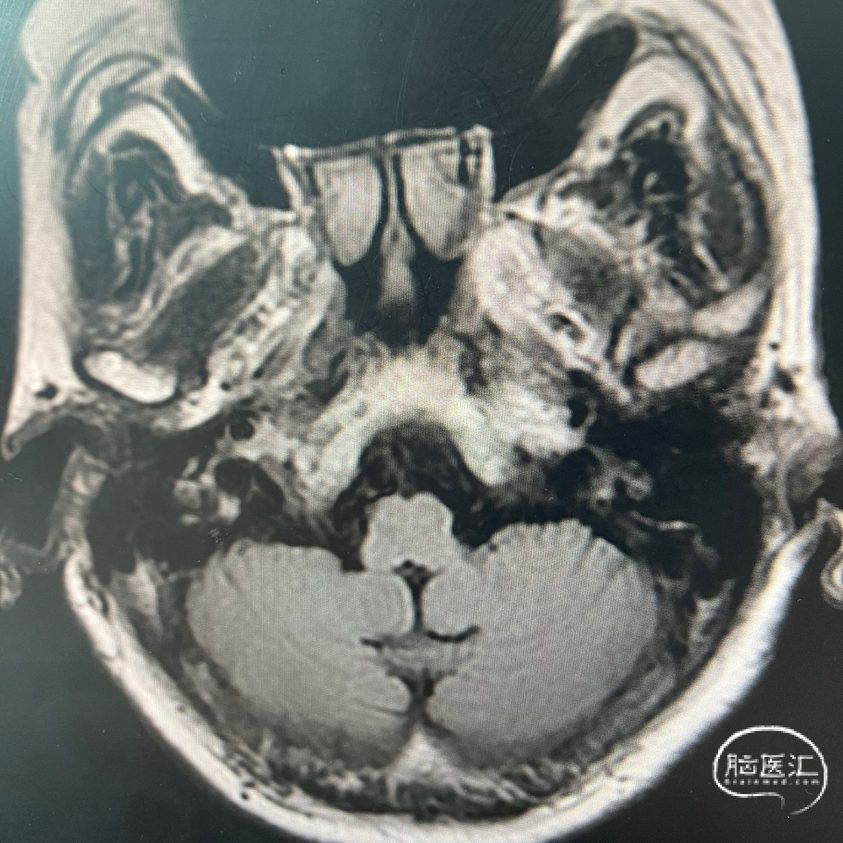

术前FLAIR

影像学表现: